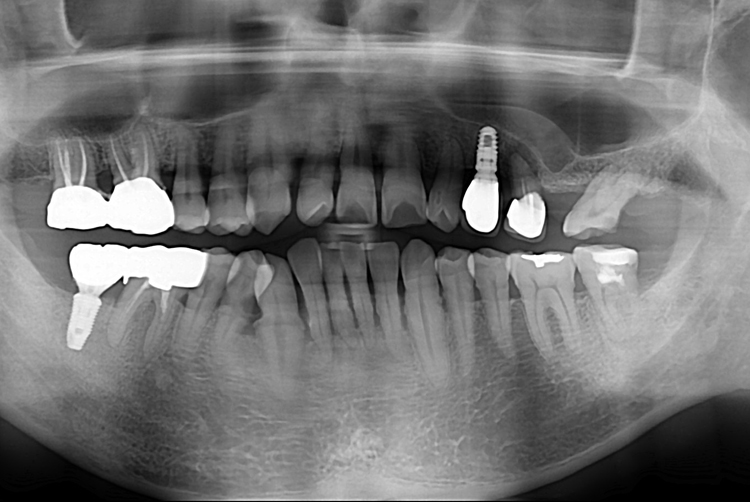

[임플란트] 어금니 임플란트

치료전 : 2019-06-05